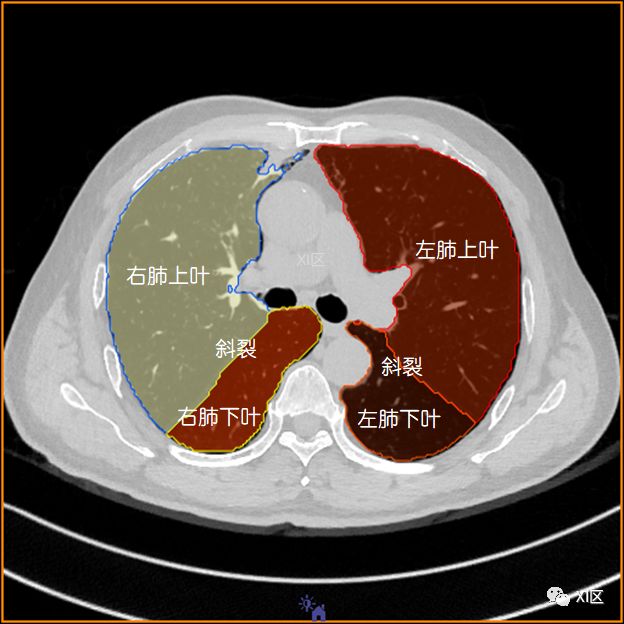

左肺借斜裂成上、下两叶;右肺借斜裂和水平裂成上、中和下叶三叶。

横断位